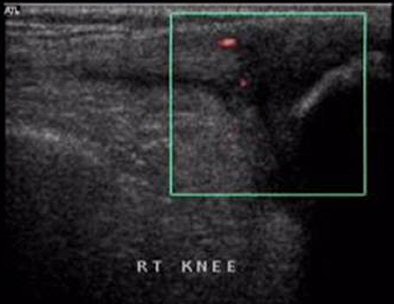

![]() |

| PDS reveals normal vascularity. |